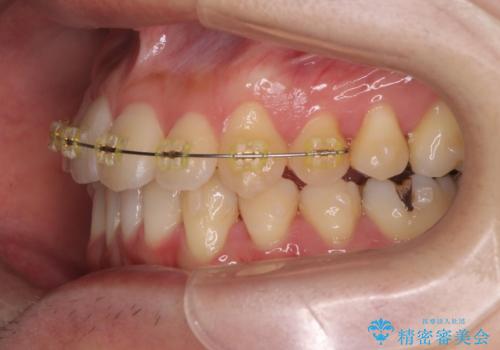

- インビザライン +部分ワイヤー矯正

すれ違いを治すのが得意な前歯部の部分ワイヤーを用いることで、治療期間を短縮することができました。

見た目の改善だけでなく、噛みやすくなったことにも満足いただくことができました。